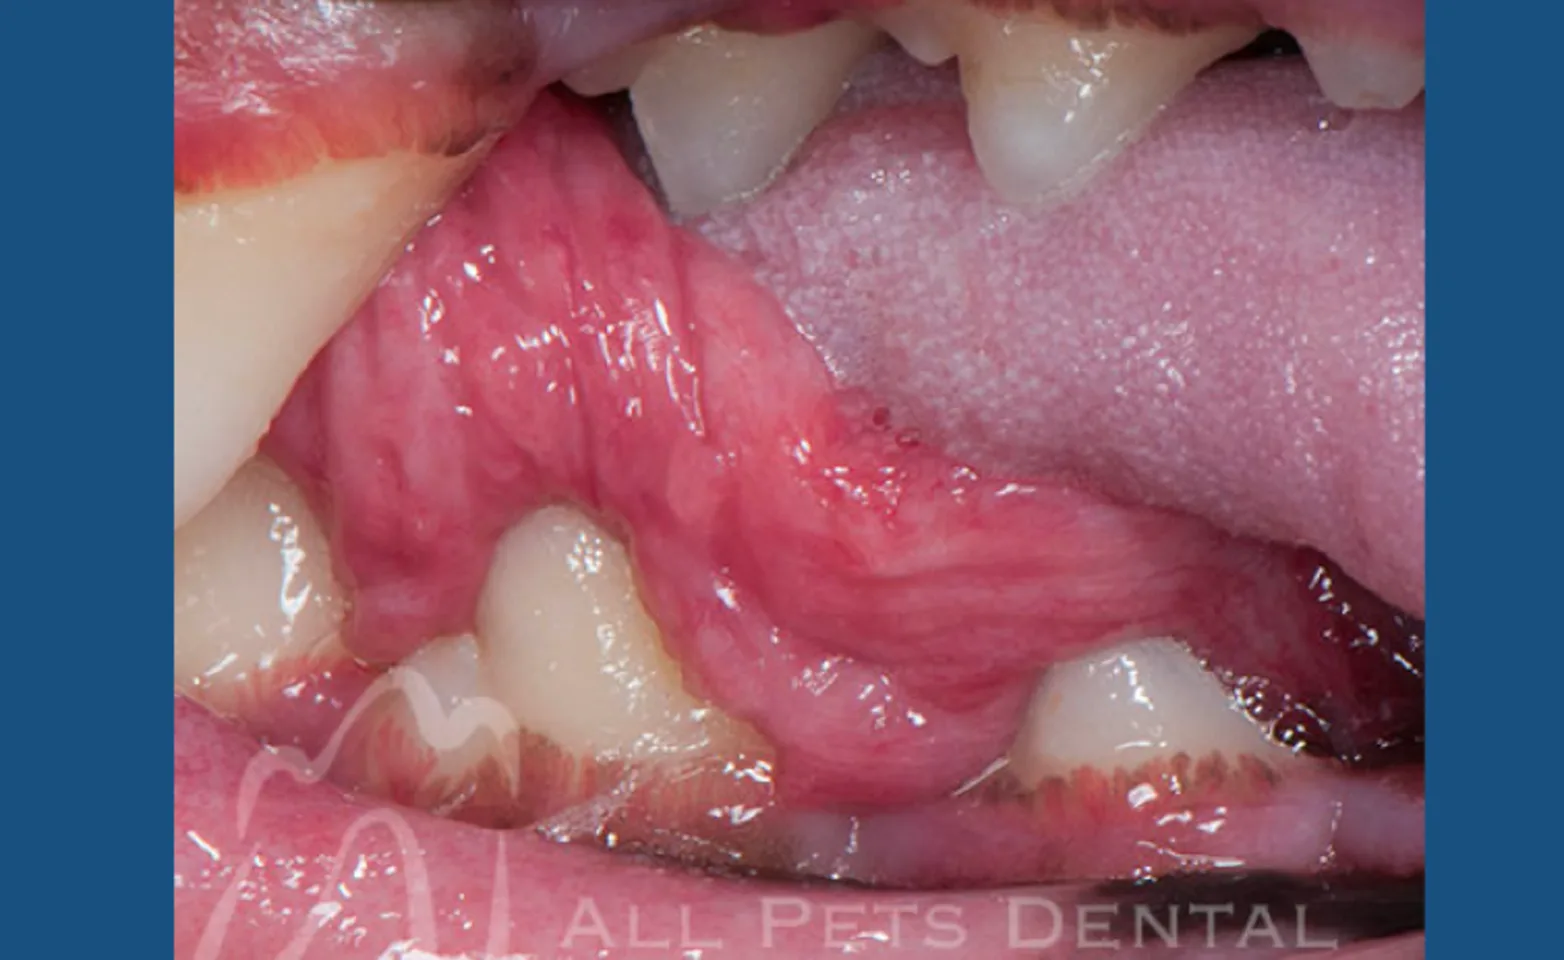

Gum chewers Lesion

Named gum chewers lesion because affected dogs appear to be chewing gum. Visibly there will be growths under the back part of the tongue. Treatment involves laser removal of the excessive tissue.